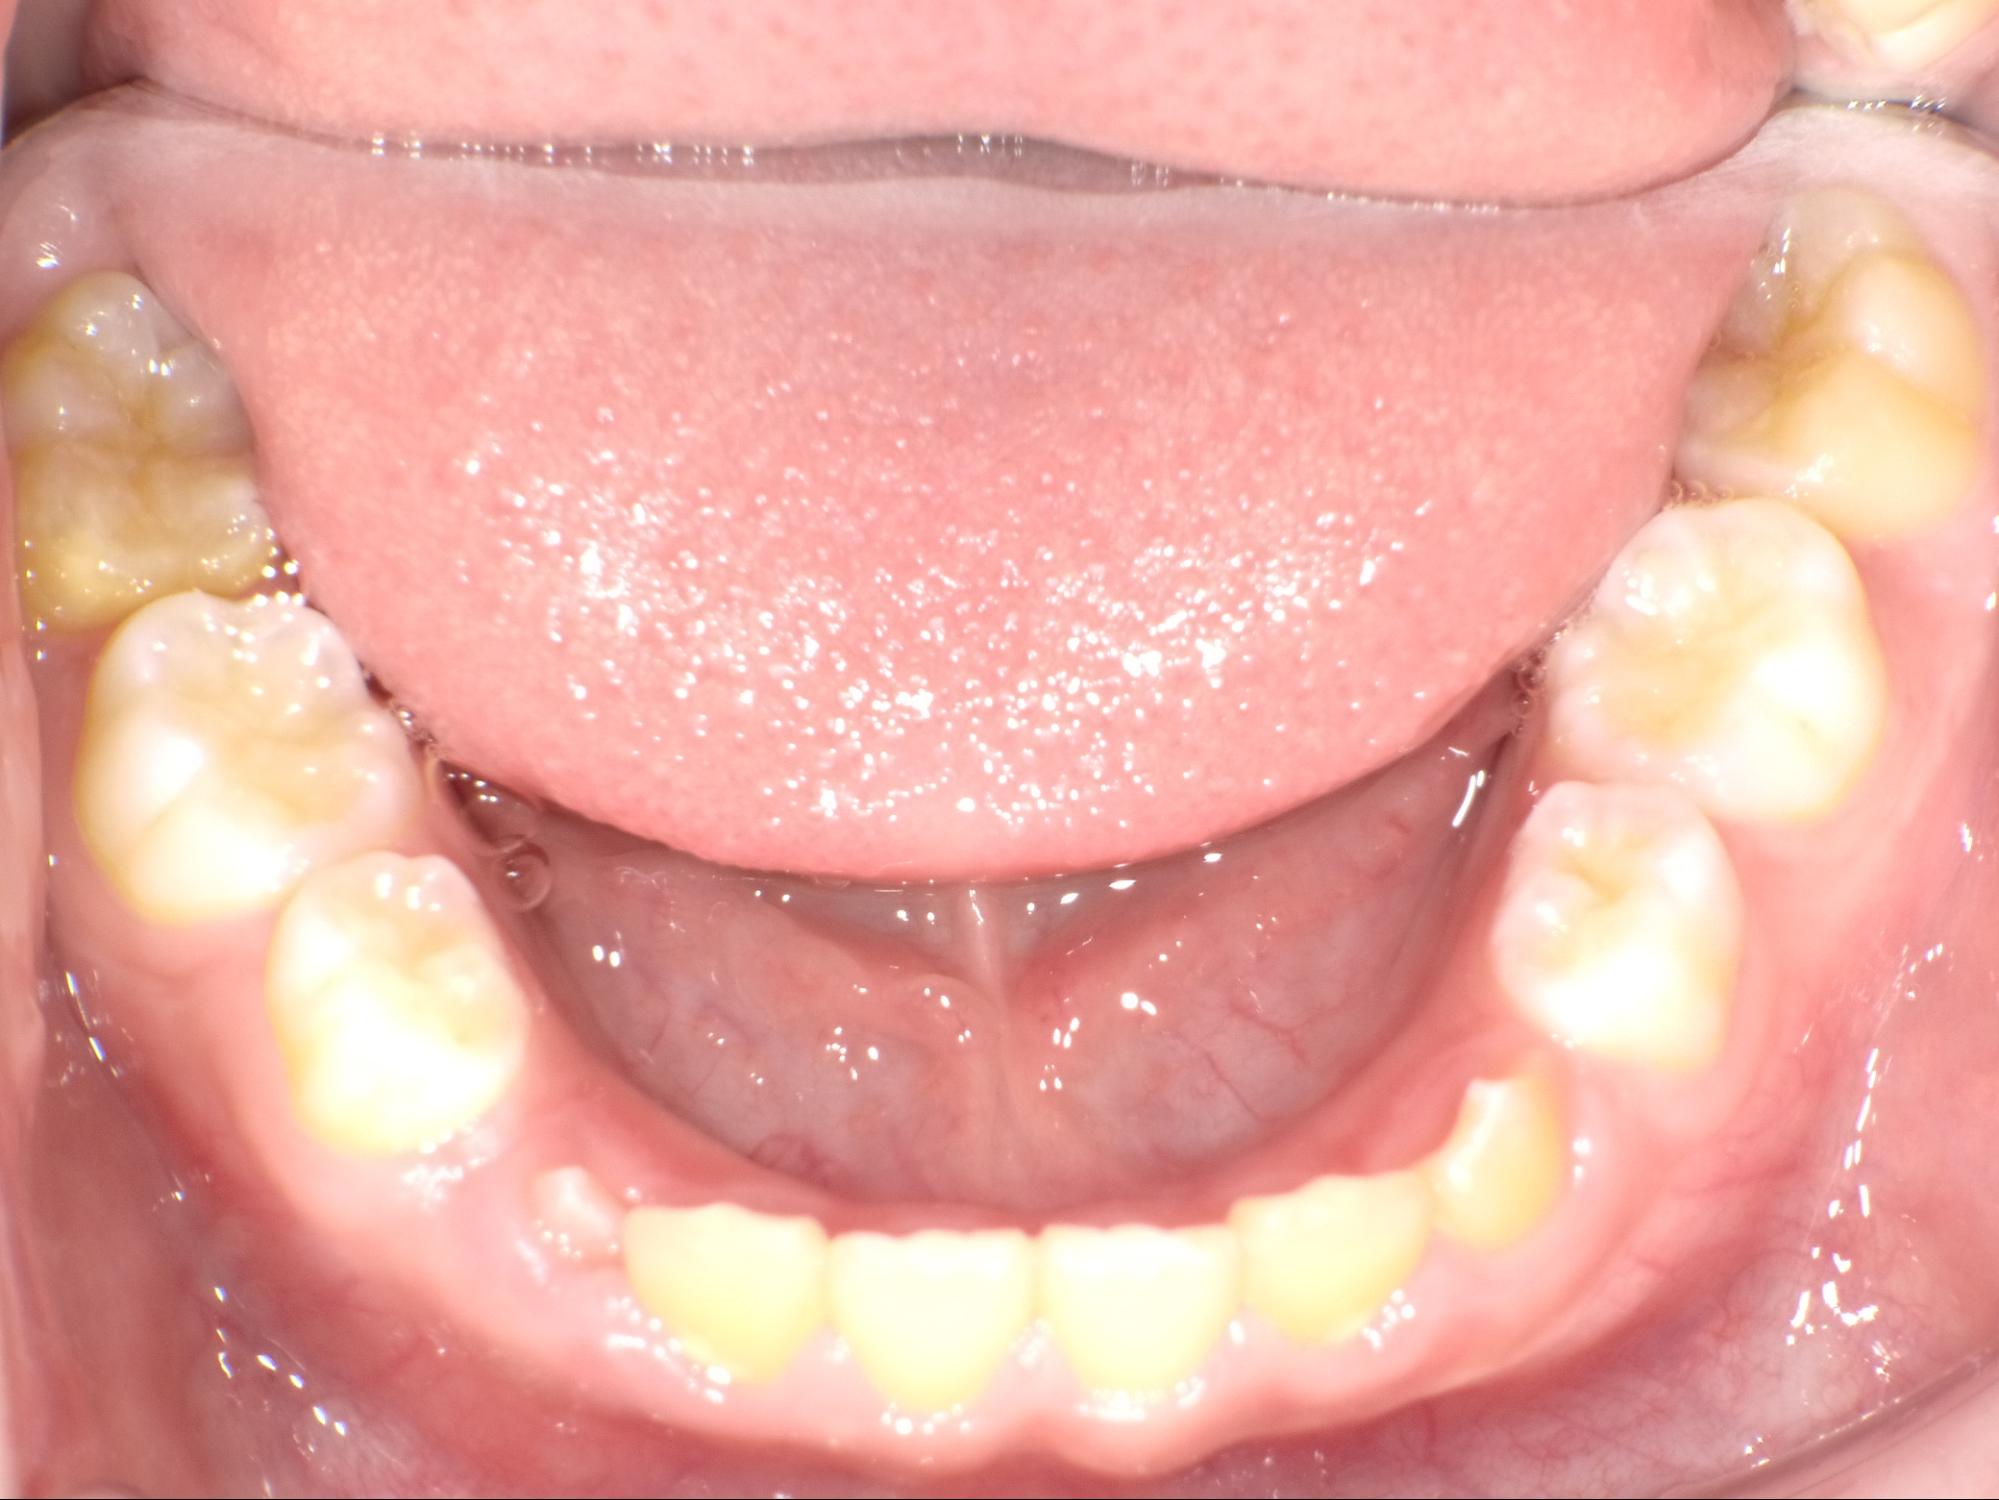

| 年齢・性別 | 男性 |

|---|---|

| 主訴 | 歯並びが気になる |

| 治療期間・回数 | 1年間 |

| 費用 | 330,000円(税込) |